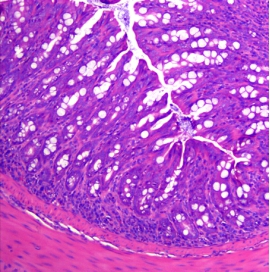

- Poor coat condition 2) Pathological Changes

- Significant shortening of the colon

- Mucosal thickening

- Lymph node enlargement

- Loss of goblet cells

- Loss of crypt structure

- Adenomatous polyps and tumor-like changes in some animals